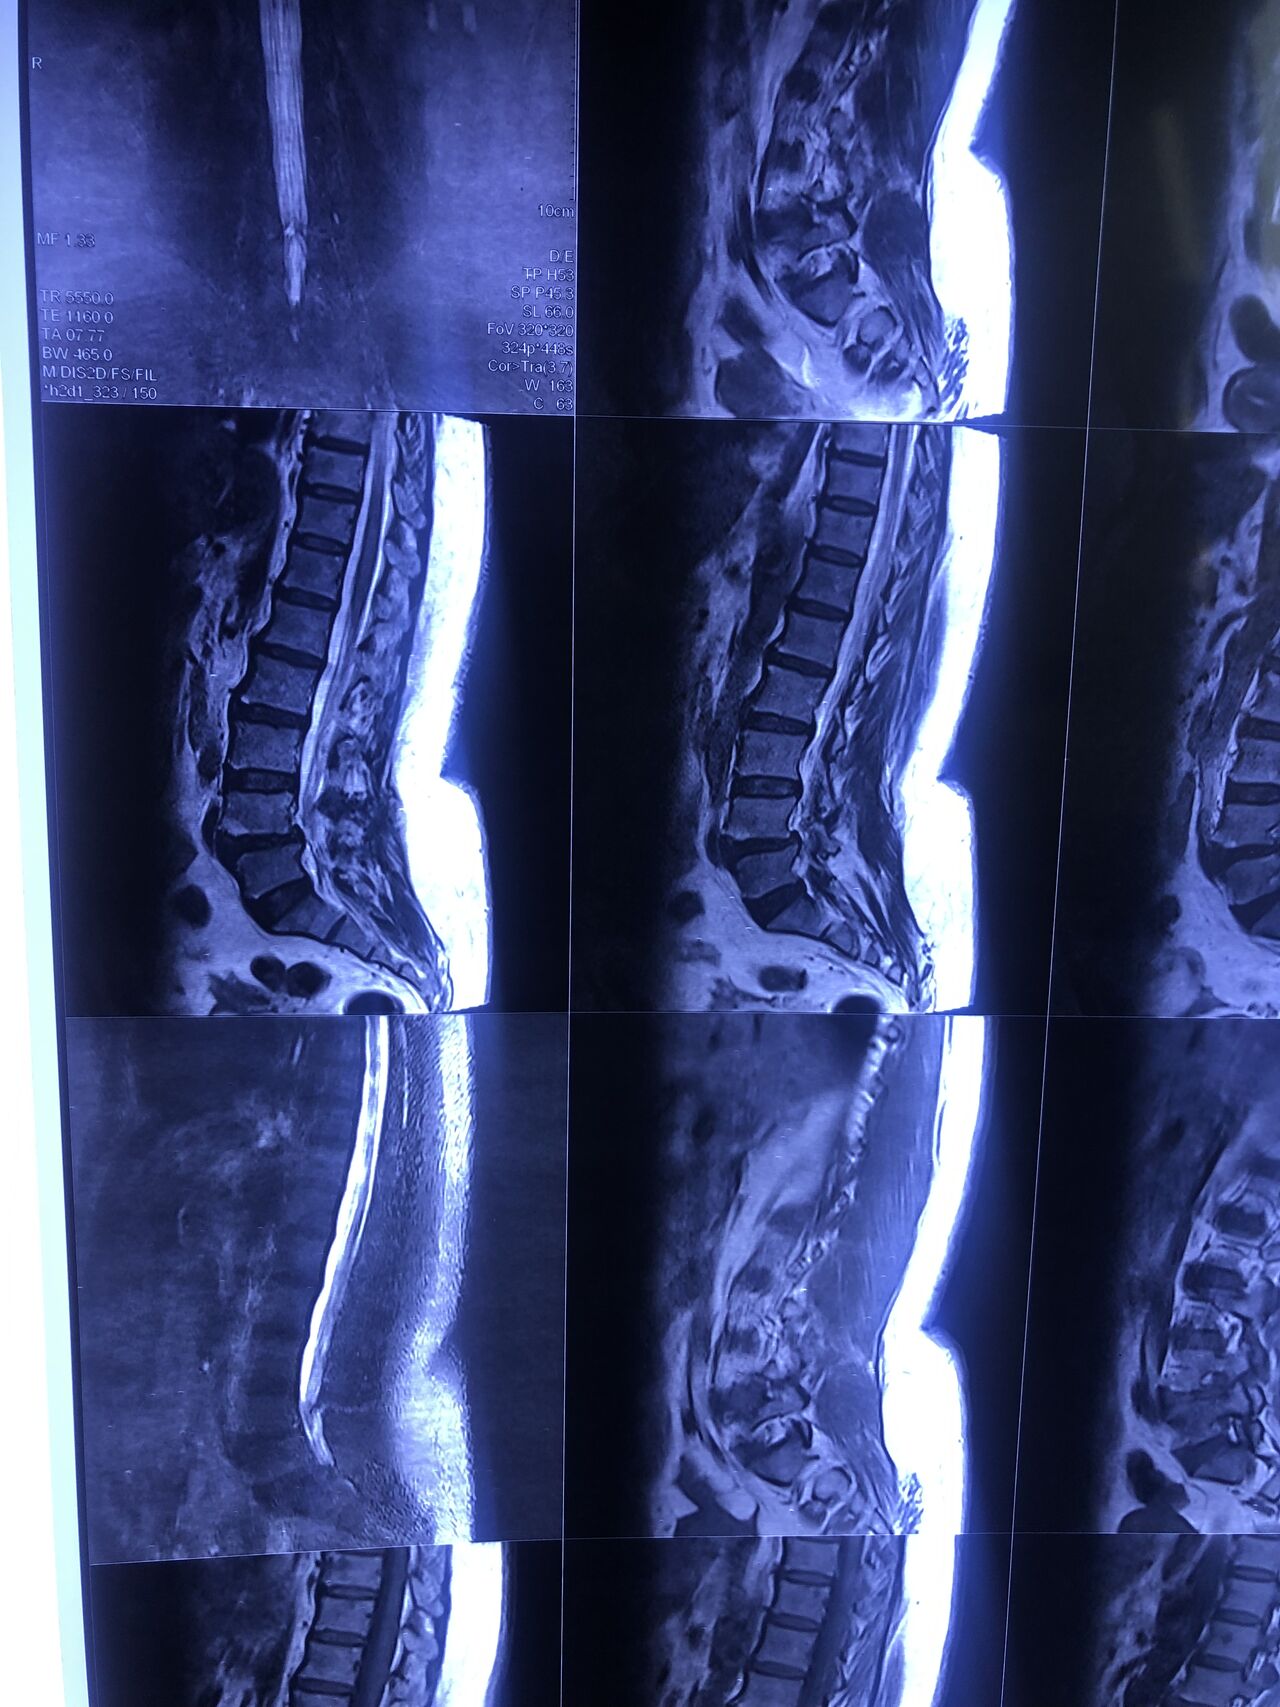

40 yrs old male patient presented to my office who had severe R gluteal pain and radicular pain along R L5-S1 now pain has reduced by 80% in his motor exam had R big toe L5 motor reduced to 4+\5 and R S1 DTR was 0 while L S1DTR was 1+

We did EMG/NCV which showed Mod- sever R L5 S1 irritation without any active axonal loss

I had to decide to refer him for surgery or not patient didn’t have any treatment meanwhile

I ordered new L/S mri

I posted his new mri and old mr

Which was 20 days ago and have posted all below

The first 12 mris had been done 20 days ago

After those first 12 MRIs i have posted new MRIs which were done yesterday

After seeing his new mri and emg/ncv and getting sure his neurological deficit is not active and progressing i told patient he doesn’t need surgery at this time and released him with some advices and exercises

Keep in mind when patient is 80-90 percent pain free and stable i would never give treatment to them just give exercises and follow up their condition